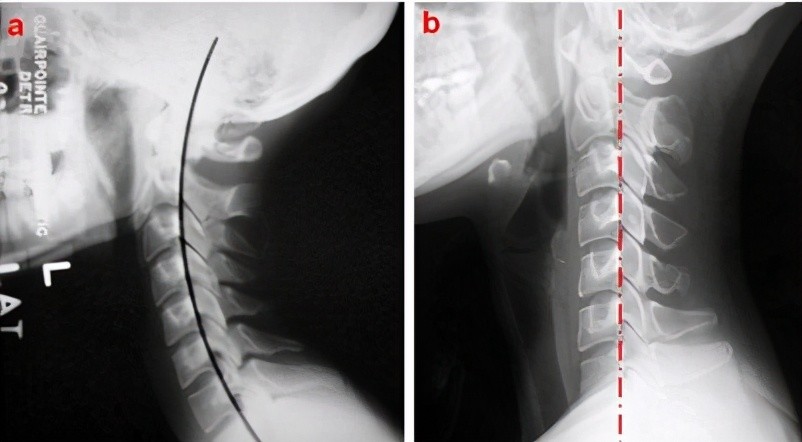

颈椎曲度变直,反屈",在颈椎过伸位,过屈位片子上可以看到颈椎相邻椎体